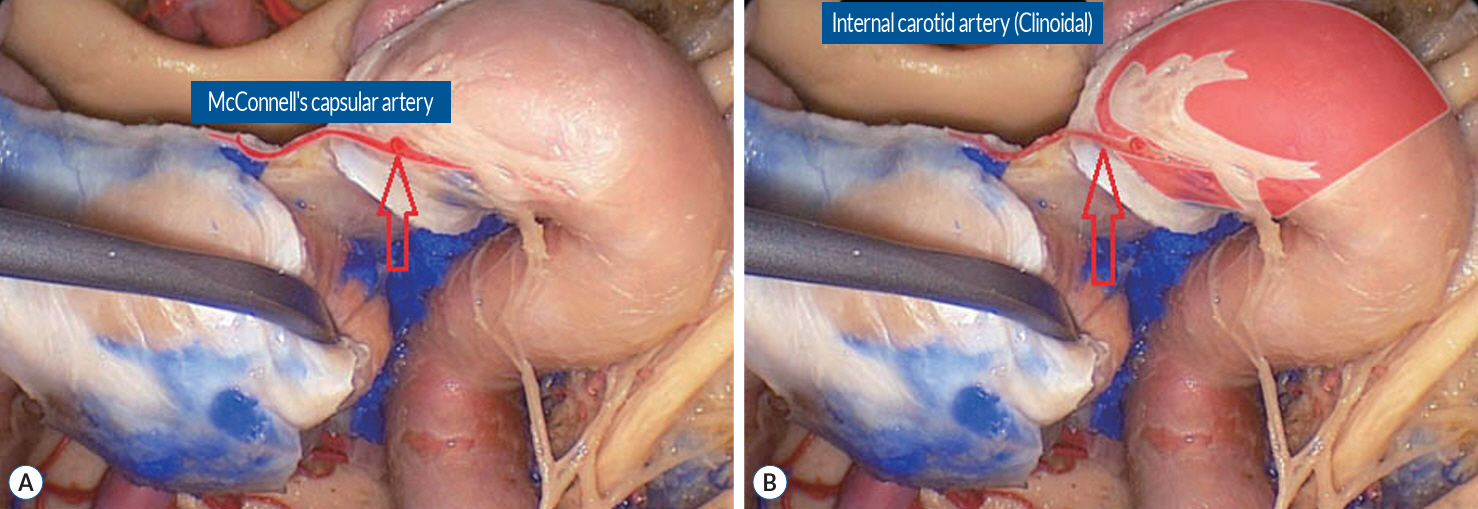

A Successful Control of the Intraoperative Bleeding from McConnell’s Artery during Fully Endoscopic Resection of Planum Sphenoidale Meningioma Using Bone Chip and Bioglue : A Case Report

- The endoscopic transsphenoidal approach is a common approach used in skull base neurosurgery to reach the sellar region. One of the intraoperative risks of this approach is intraoperative bleeding out of the carotid artery. Gentle drilling can prevent carotid artery injury. However, injury to smaller branches, such as the McConnell’s capsular artery, which is located within the surgical corridor, is more difficult to prevent. If such an injury is within the junction to the main trunk of the carotid artery, there will be a small circular defect in this area. This can result in massive blood loss and should be closed surgically immediately. We describe a clinical case of intraoperative bleeding from the McConnell’s artery originating from the carotid arterial segment (C4) in a 78-year-old female patient operated on for planum sphenoidale meningioma via endoscopic transsphenoidal approach, as well as provide a technical note on a possible technique for bleeding control in such cases. Pinpoint carotid bleeding as a result of intraoperative injury can be stopped by wedging a bone fragment in the carotid canal and fixing it in that position with histoacryl glue at the defect site.